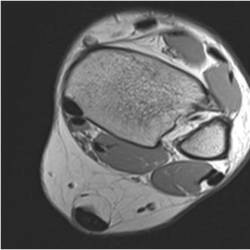

Physician Assistant Lower Limb and Thorax Written Examination - Radiology Pool

Gallery of Unlabled Radiographs from Lecture (Dr. French) - 2020

Click a thumbnail to enter the gallery display. Click the file name link at the bottom left of the gallery display to view the image at high resolution.